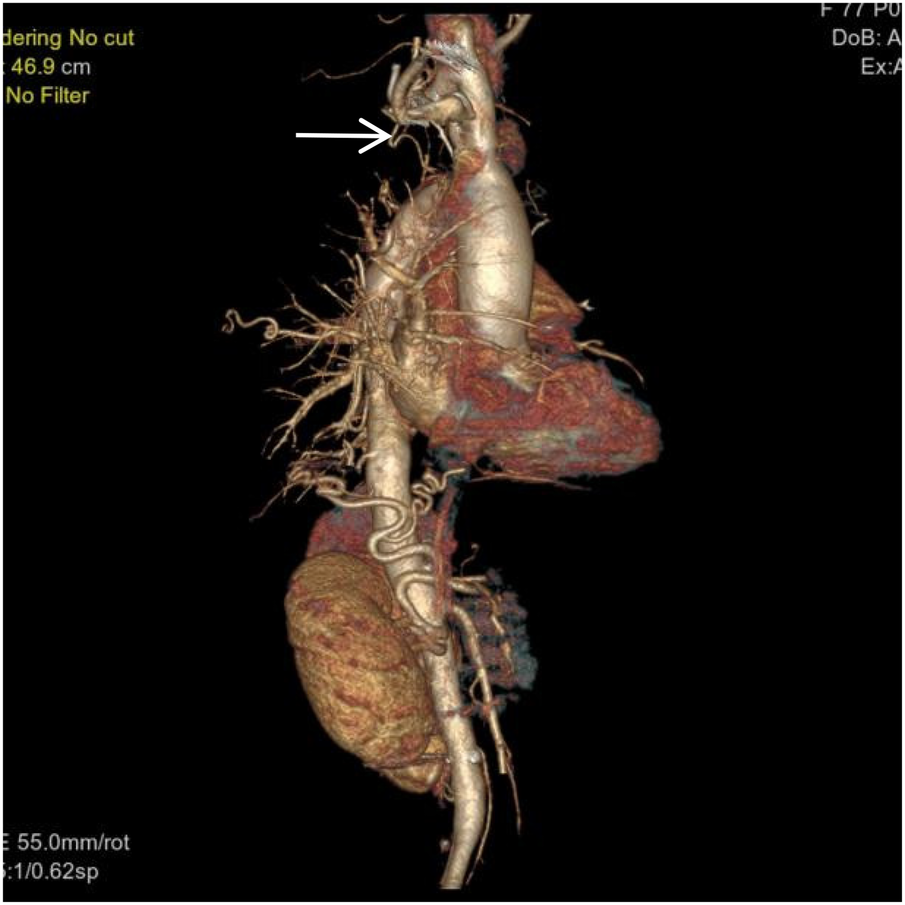

Figure 4

VR image shows a branch of the right subclavian artery entering the right lung (white arrow).

Thoracoabdominal aortic CTA and chest CT findings are illustrated in Figures 1–14. There was no evidence of aortic dissection. The right pulmonary artery was absent distal to approximately 3 cm from the bifurcation, with a smooth and rounded defect margin. The main pulmonary artery and its major branches showed no abnormal densities. No right pulmonary artery branches were observed in the right lung. Multiple tortuous arterial branches from the right subclavian artery, descending aorta, and right renal artery supplied the right lung. The right hemithorax was smaller, with localized pleural thickening and adhesions bilaterally. Multiple bronchiectasis with thickened walls and patchy, nodular, and linear opacities encircled the right lung. Increased translucency and several hyperlucent regions were visible in the left lung. CT imaging findings demonstrated: 1. Congenital absence of the right pulmonary artery (RPA), with the right lung supplied by collateral circulation originating from the right subclavian artery, right intercostal arteries, and the right renal artery. 2. Right pulmonary hypoplasia, bronchiectasis of the right lung, accompanied by infection and partial consolidation in the right upper lobe, compensatory hyperinflation of the left lung, and multiple bullae in the left lung. 3. Bilateral localized pleural thickening and adhesions. 4. Osteoporosis and mild flattening of the T6 vertebra and compression fractures of T11 and T12.